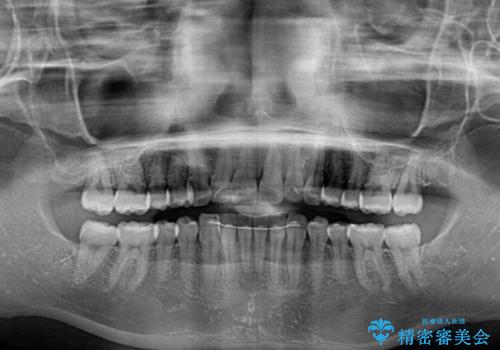

- 1本飛び出した前歯を治したいとのことで来院された患者様です。

歯列全体の拡大とIPR(歯と歯の間を削る)によってデコボコが解消するようにし、さらにゴムかけを活用して右側の咬み合わせ位置を変えるように設計し、インビザラインにより治療を行うこととしました。

後方移動に際し、上下顎の親知らずは3本とも抜歯することとしました。